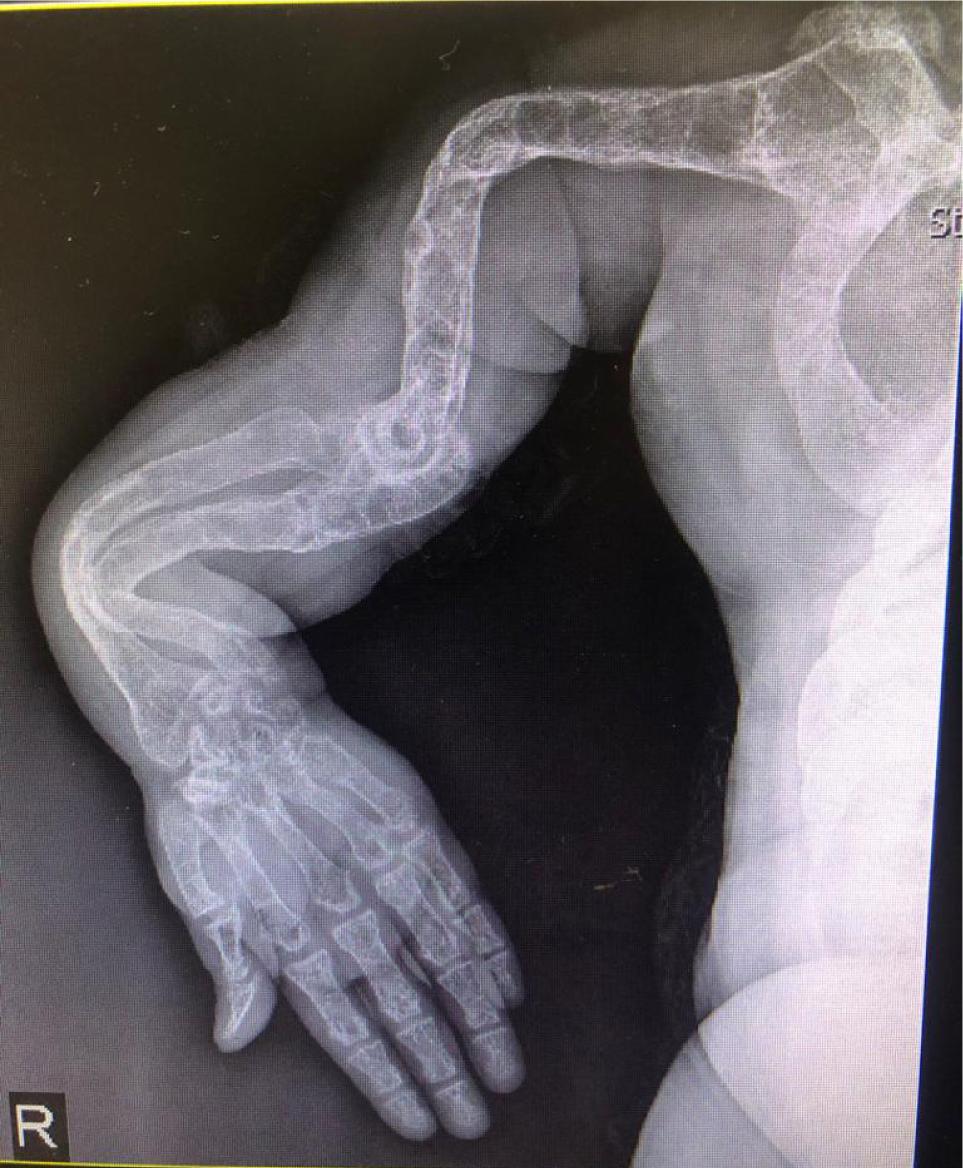

Clinical examination established diagnosis of rickets. The patient depicted severe bowing of the upper and lower limbs and marked generalized osteopenia (Figure 2). Bony fusion and significant osteoarthritis was observed in the larger joints, with apparent presence in his knees. Angulation of the carpal bones and squaring in the head of the metacarpal bones was demonstrated. Severe deformity of the rib cage, inward bowing of the ribs, and marked kyphoscoliosis were also analyzed.

Figure 2: X-ray reveals severe bowing of the upper and lower limbs and marked generalized osteopenia.

Multiple musculoskeletal manifestations have been described in Wilson’s disease. Early onset of osteoarthritis (OA) is the most common musculoskeletal manifestation. Osteoarticular changes associated with Wilson’s disease include osteoporosis, osteomalacia, and degenerative joint diseases, especially of the knees and wrists. Radiography shows bone fragmentation, osteoarthritis, joint capsule calcification, chondrocalcinosis, osteochondritis dissecans (OCD), and subarticular cysts. Some spinal involvements could also be encountered in these patients such as vertebral body squaring, early lumbar osteoarthritis, and osteochondritis. The present patient demonstrated severe bowing deformity of the upper and lower limbs, metaphyseal widening along with marked generalized osteopenia. Degenerative changes in joint, including large osteophytes, patellofemoral fusion, loss of joint space, and deformities, could be observed in the knees. Similar changes are apparent in other large joints. In the wrists, angulation of the carpal bones and squaring in the head of metacarpal bones are discovered. Chest X-ray evidenced severe deformity of the rib cage, inward bowing of the ribs, and marked kyphoscoliosis. Both hemidiaphragms are elevated and limited space was discovered on left of the lungs.